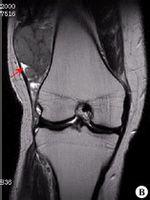

滑膜肉瘤是源于关节、滑膜及腱鞘滑膜的软组织的恶性肿瘤。以四肢的大关节为好发部位,也可发生于前臂、大腿、腰背部的肌膜和筋膜上。主要临床症状为局部肿胀、肿块、疼痛,活动受限为主。以手术治疗为主。